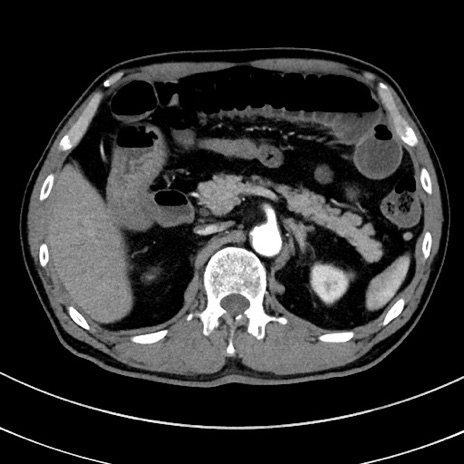

症例8(横断像)

【症例】 60歳代男性

【主訴】 黒色吐物

【現病歴】 4日前から嘔気自覚、2日前の朝食後にも嘔気あり、自分で手で嘔吐反射起こし嘔吐したところ血が混ざっていたため受診。

【既往歴】 5年前汎発性腹膜炎を伴う急性虫垂炎で手術、高血圧、前立腺肥大症、高脂血症

【身体所見】 腹部正中に手術癩痕あり 腹部平坦・軟圧痛なし膨満感あり

【データ】WBC 8400、CRP 4.54